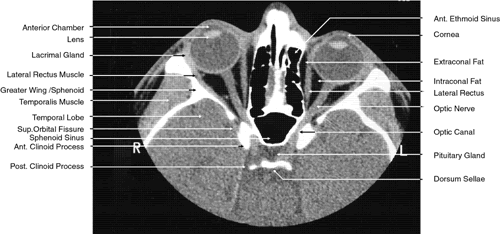

2D CT imaging is most frequently performed in the axial plane (Fig. 2). The bony anatomy of the orbit, optic canal, and intracranial cavity determines the exact orientation of this plane to provide the best visualization of both bone and soft tissue. The bony orbit is shaped like a quadrilateral pyramid lying on its side and with its base facing anteriorly. The medial orbital walls are almost parallel, although they tend to converge toward the midline in their posterior aspect. The lateral orbital walls diverge at approximately 45 degrees to the midline. The orbital axis is about 23 degrees divergent from the midline. The orbitomeatal line (Reid's baseline or the Frankfurt-Virchow line) is an important radiologic landmark for imaging the orbital structures. It is a line that extends from the upper margin of the external auditory meatus to the inferior orbital rim. The orbital floor is at approximately a -20-degree angle with this line, and the optic canal is at approximately a -30-degree angle with this line. Axial scans of the orbit are performed parallel to the orbitomeatal line, in contrast to axial scans of the intracranial contents, which are performed in a plane parallel to the orbital roof, which is at a + 30-degree angle to this line. The optic chiasm is also best imaged in a plane parallel to the orbitomeatal line. Although both the optic canal and nerve can be adequately visualized with axial scans parallel to this plane, scans of these structures are more precisely performed if the image plane is at a -30-degree angle to this line with the globe in upward gaze. This straightens the nerve and places its axis in the same plane as the canal. The optic canal of infants and young children is at approximately a -20-degree angle with the orbitomeatal line, and in these age groups the scanning angle is appropriately modified for precise imaging of this structure. For orbital scans a 3-mm slice thickness is usually employed; for scanning the optic nerve and canal, a 1.5-mm slice thickness is recommeded to image these structures completely (Fig. 3). Thin-slice technique is helpful in reducing the effects of partial volume averaging, thus improving image resolution of small-diameter structures such as the optic nerve. In contrast, axial scans of the intracranial contents are usually 5- or 10-mm thick slices, although thinner slices are often used when imaging structures such as the cavernous sinus, suprasellar cistern, pituitary gland, and optic chiasm. Generally, the radiation dose associated with thin-cut CT imaging is 30 mGy (using 3-mm slice increments) to 80 mGy (using consecutive 1.5-mm scans), which is considerably less than complex motion tomography of the facial area and similar to standard plane film head scans.

Fig. 2. Axial computed tomography scan at the level of midorbit.

Fig. 3. Axial computed tomography scan of the orbital apex and optic canal.